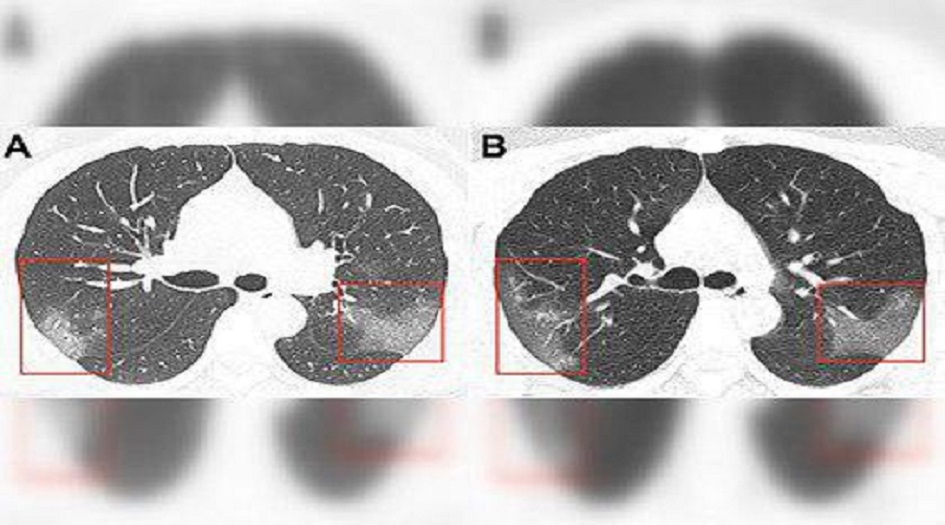

الصحة - الكوثر: عرض الأطباء الصينيون صورا لرئتي مصاب بفيروس كورونا 2019-nCoV لمريضة تبلغ من العمر 33 عاما.

وعلى أساس الخصائص الوبائية والأعراض السريرية ونتائج التصوير الطبقي المحوري، تم تشخيص إصابتها بالالتهاب الرئوي 2019-nCoV.

وبعد ثلاثة أيام من العلاج، اتسعت رقعة المنطقة المصابة من الرئتين (الصورة ب) – في الصور تبدو معتمة.